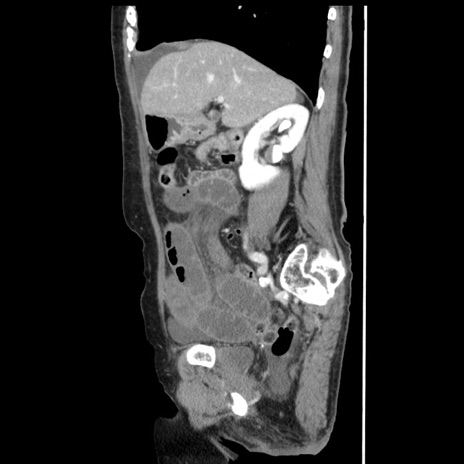

症例1(矢状断像)

【症例】80歳代女性

【主訴】腹痛

【現病歴】8時間前から腹痛あり来院。

【既往歴】糖尿病、脂質異常症、子宮体癌にて子宮全摘術

【身体所見】意識清明・会話良好だが腹痛で苦悶様、全腹部にわたって反跳痛と圧痛あり

【データ】WBC 13600、CRP 0.14、LDH 224、CK 90